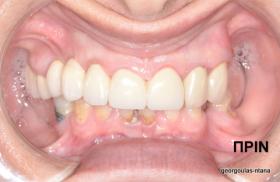

ΑΝΟΙΚΤΗ ΑΝΥΨΩΣΗ ΙΓΜΟΡΕΙΟΥ Κ ΤΟΠΟΘΕΤΗΣΗ 3 ΕΜΦΥΤΕΥΜΑΤΩΝ

Στην ασθενή αυτή πραγματοποιήθηκε ανοικτή ανύψωση ιγμορείου άνω αριστερά. Σε πρώτη φάση πραγματοποιήθηκε η οστική αύξηση και 6 μήνες μετά τοποθετήθηκαν 3 εμφυτεύματα. Τόσο στην πανοραμική όσο και στην τομογραφία κωνικής δέσμης (CBCT) που πραγματοποιήθηκαν 6 μήνες μετά την ανύψωση είναι εμφανής ο σχηματισμός οστού. Η τελευταία ακτινογραφία και φωτογραφία λήφθηκαν 5 χρόνια μετά την προσθετική αποκατάσταση.